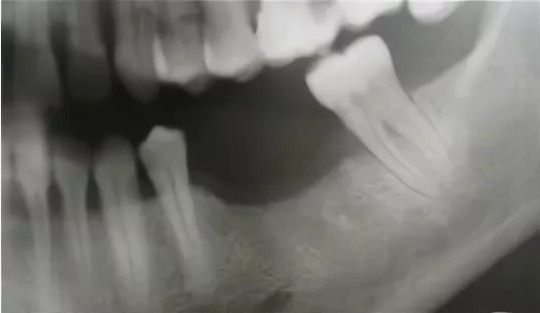

Окончательное решение принимается после 3D-томографии: снимок показывает точный объем кости, ее плотность, расположение пазух и нервов. Диагностика занимает 15–20 минут, и после нее врач анализирует вашу клиническую картину и дает рекомендации.

Сначала — 3D-томография. Она занимает около 15 минут и сразу показывает реальную картину: где кости достаточно, где есть дефицит и насколько он критичен. Врач объясняет, как проходят нервы и расположены гайморовы пазухи, и что это значит именно для вас.